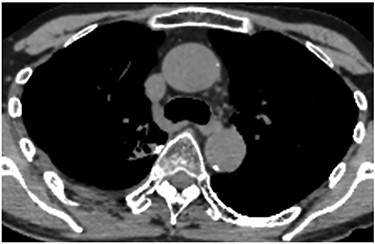

A 60-year-old man underwent right apical and posterior segmentectomies via VATS for early-stage lung cancer. The bronchus and pulmonary parenchyma were divided by endoscopic staples (Echelon®; Ethicon Endo-Surgery). The resected tumour was 1.5 cm in the longest diameter and pathologically diagnosed as Stage IA adenocarcinoma. The patient was discharged uneventfully on eighth day after surgery. Chest radiography revealed no significant findings, and laboratory data were within the normal ranges on the 14th day after discharge at a scheduled visit to the outpatient clinic. However, the patient was transported by ambulance to our hospital owing to a sudden onset of chest pain and dyspnoea on the 32nd day after discharge. He developed hypotension and tachycardia with systolic blood pressure of 50 mmHg and heart rate of 114 beats/min. The haemoglobin concentration level, which had been 12.3 mg/dl on the 14th day after discharge, decreased by 8.7 mg/dl. Chest radiography revealed a massive right pleural fluid, and enhanced computed tomography (CT) showed an extravasation of contrast media near the fifth thoracic vertebra (Fig. 1). The patient was diagnosed with haemothorax and an emergency operation was performed. Thoracoscopic examination revealed massive blood coagulation in the right thoracic cavity, with no adhesions. After removal of the coagulation, continuous active bleeding from the intercostal artery was found near the fifth thoracic vertebra in the vicinity of a stump of the bronchus divided by a staple (Supplementary Video 1). A thoracotomy through the fifth intercostal space was therefore performed to achieve haemostasis, and the bleeding was stopped by suturing using a 4–0 nonabsorbable monofilament ligature. In addition, the bleeding point was covered with a collagen-fibrin patch (Tachosil®). The posterior part of the staple line of the lung parenchyma adjacent to the bleeding point under full inflation was partly exposed, whereas the bronchial stump was covered with lung. Therefore, the scratching created by the staples was assumed to cause haemothorax. The total amount of haematoma in the right thoracic cavity and the intraoperative blood loss was 3980 g. Postoperative CT confirmed that the stapler dividing the lung parenchyma directly faced the bleeding point beside the fifth vertebra (Fig. 2). The patient progressed satisfactorily after the reoperation and was discharged on ninth day after reoperation.

Enhanced chest CT showing an extravasation of contrast media near the fifth thoracic vertebra.